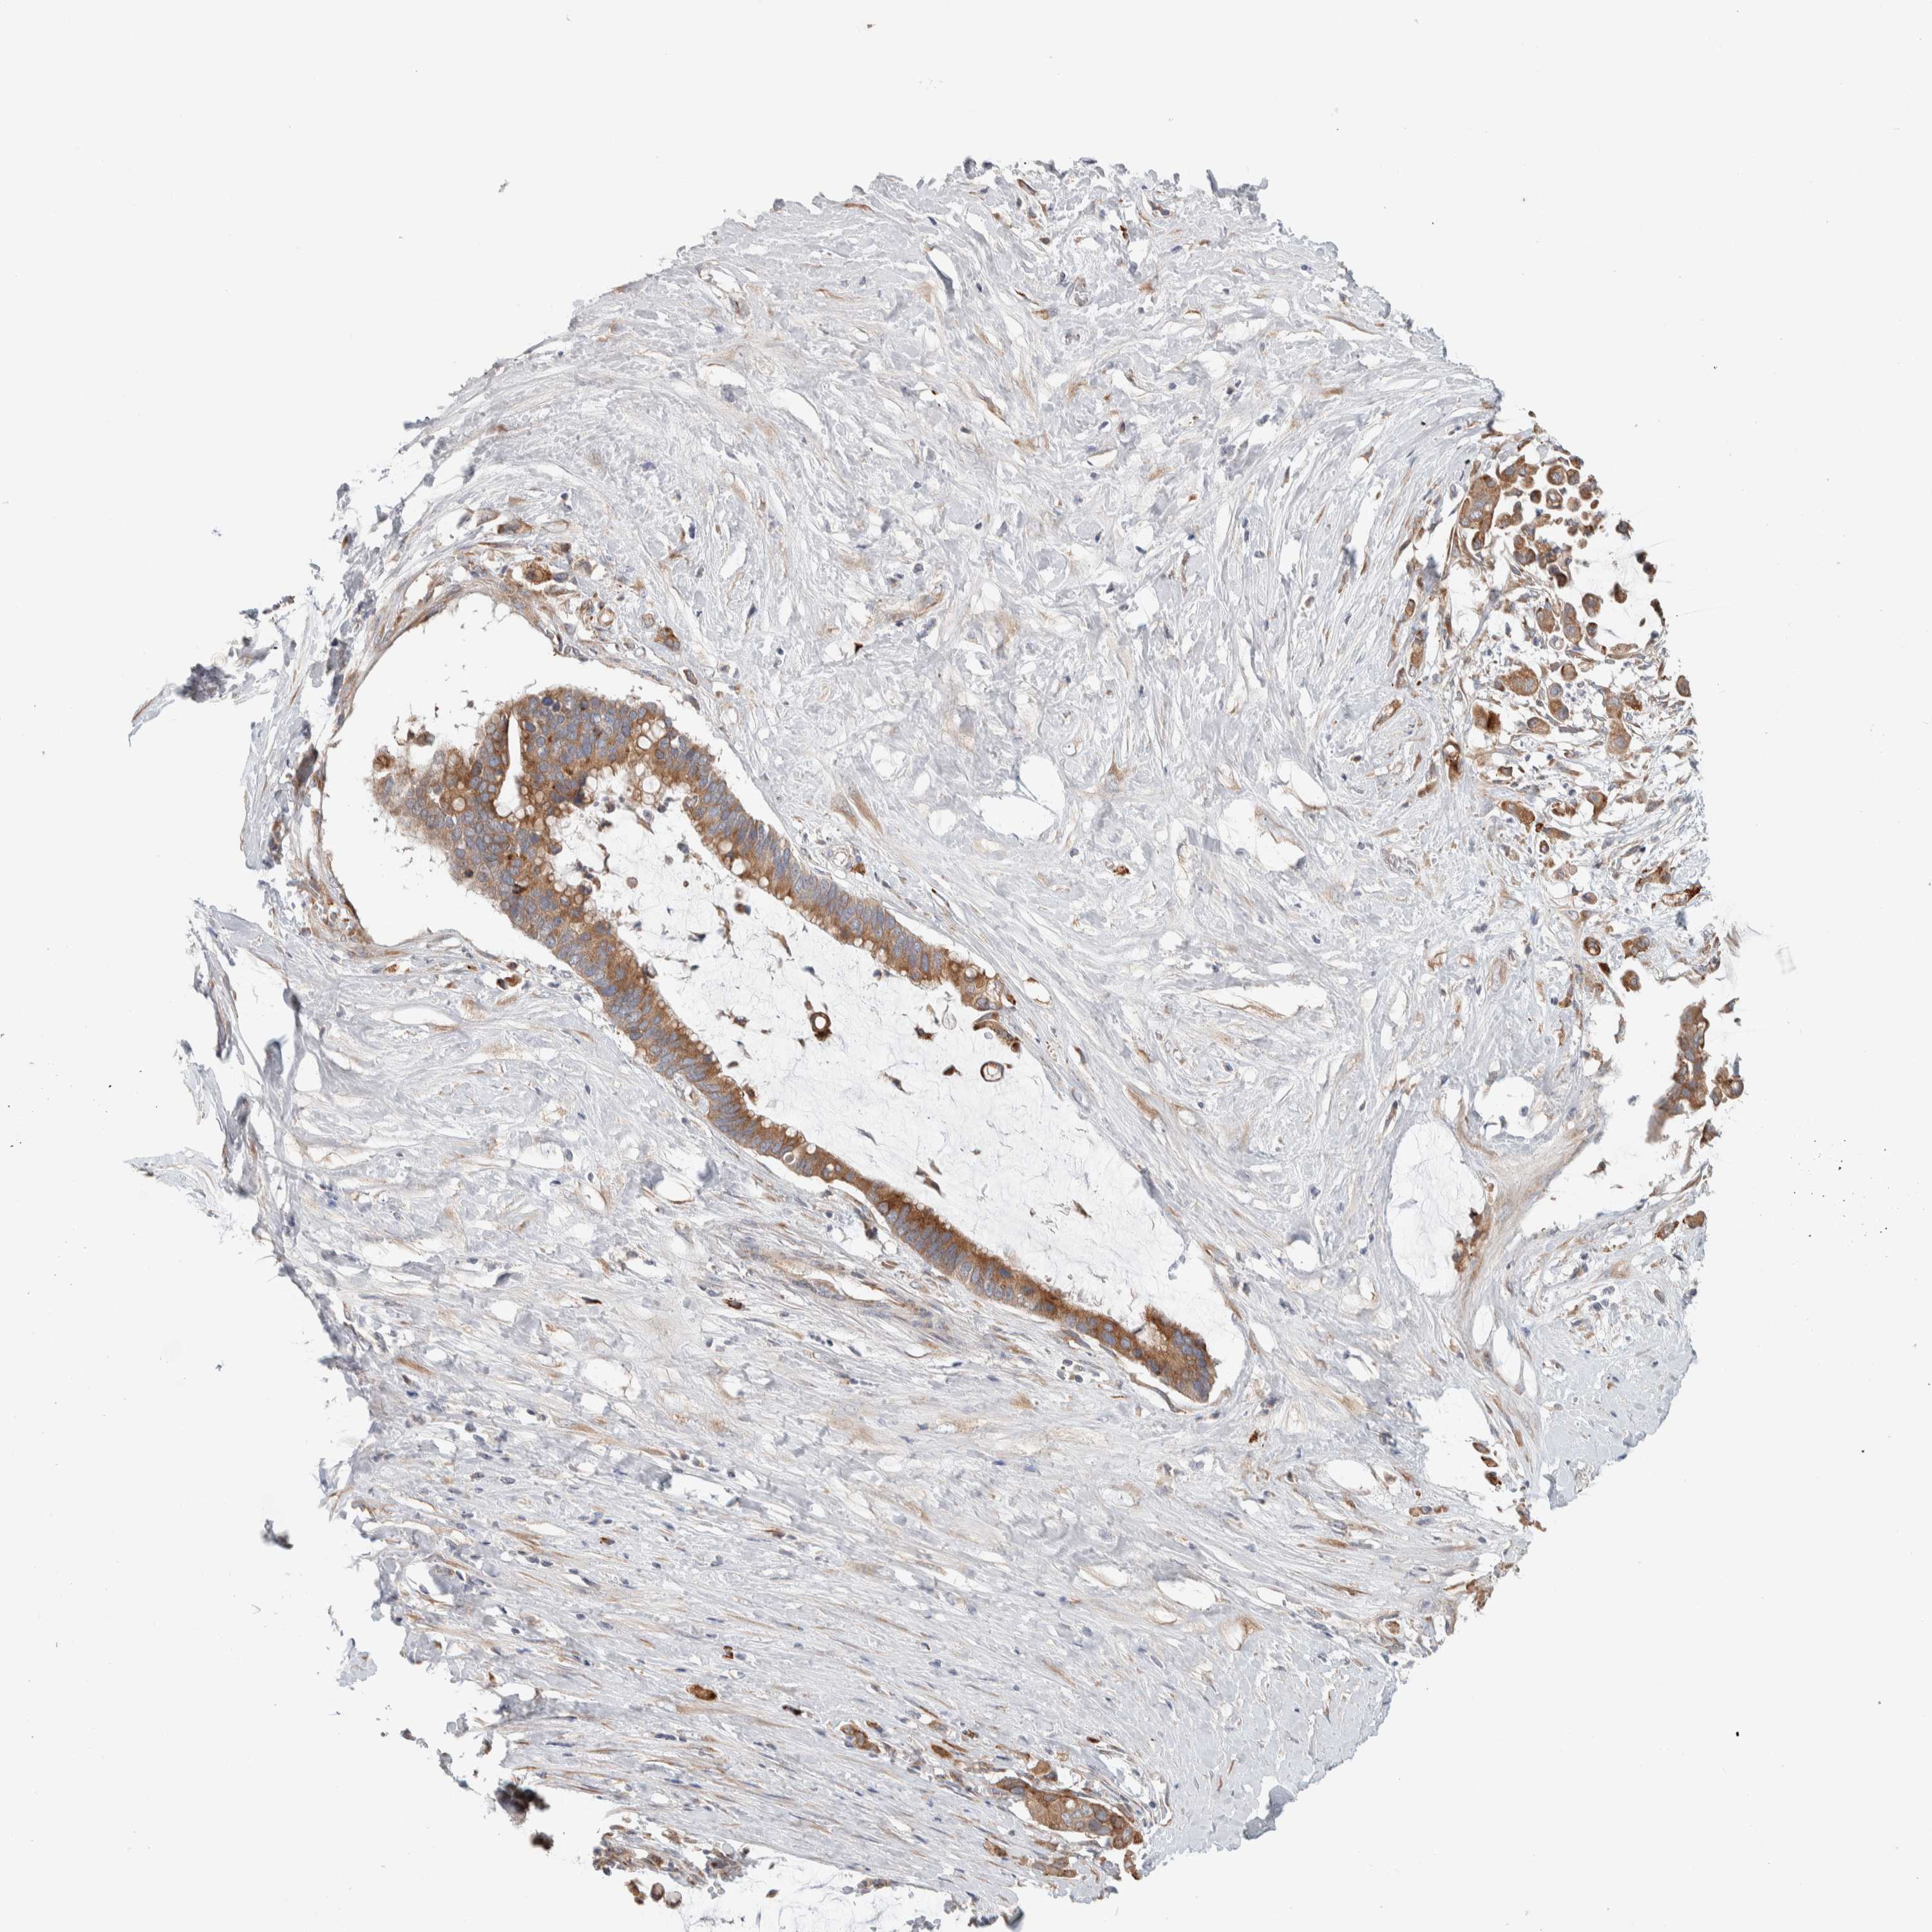

PANCREATIC CANCER - Protein expressioni

A mouse-over function shows sample information and annotation data. Click on an image to view it in a full screen mode. Samples can be filtered based on level of antibody staining by selecting one or several of the following categories: high, medium, low and not detected. The assay and annotation is described here.

Note that samples used for immunohistochemistry by the Human Protein Atlas do not correspond to samples in the TCGA dataset.

Antibody stainingi

Antibody staining in the annotated cell types in the current human tissue is reported as not detected, low, medium, or high, based on conventional immunohistochemistry profiling in selected tissues. This score is based on the combination of the staining intensity and fraction of stained cells.

Each image is clickable and will lead to virtual microscopy that enables deeper exploration of all samples and also displays staining intensity scores, fraction scores and subcellular localization as well as patient and tissue information for each sample.

Antibody HPA024291

Antibody CAB018652

Staining

High

Medium

Low

Not detected

Intensity

Strong

Moderate

Weak

Negative

Quantity

>75%

75%-25%

<25%

None

Location

Nuclear

Cytoplasmic/membranous

Cytoplasmic/membranous,nuclear

Adenocarcinoma, NOS